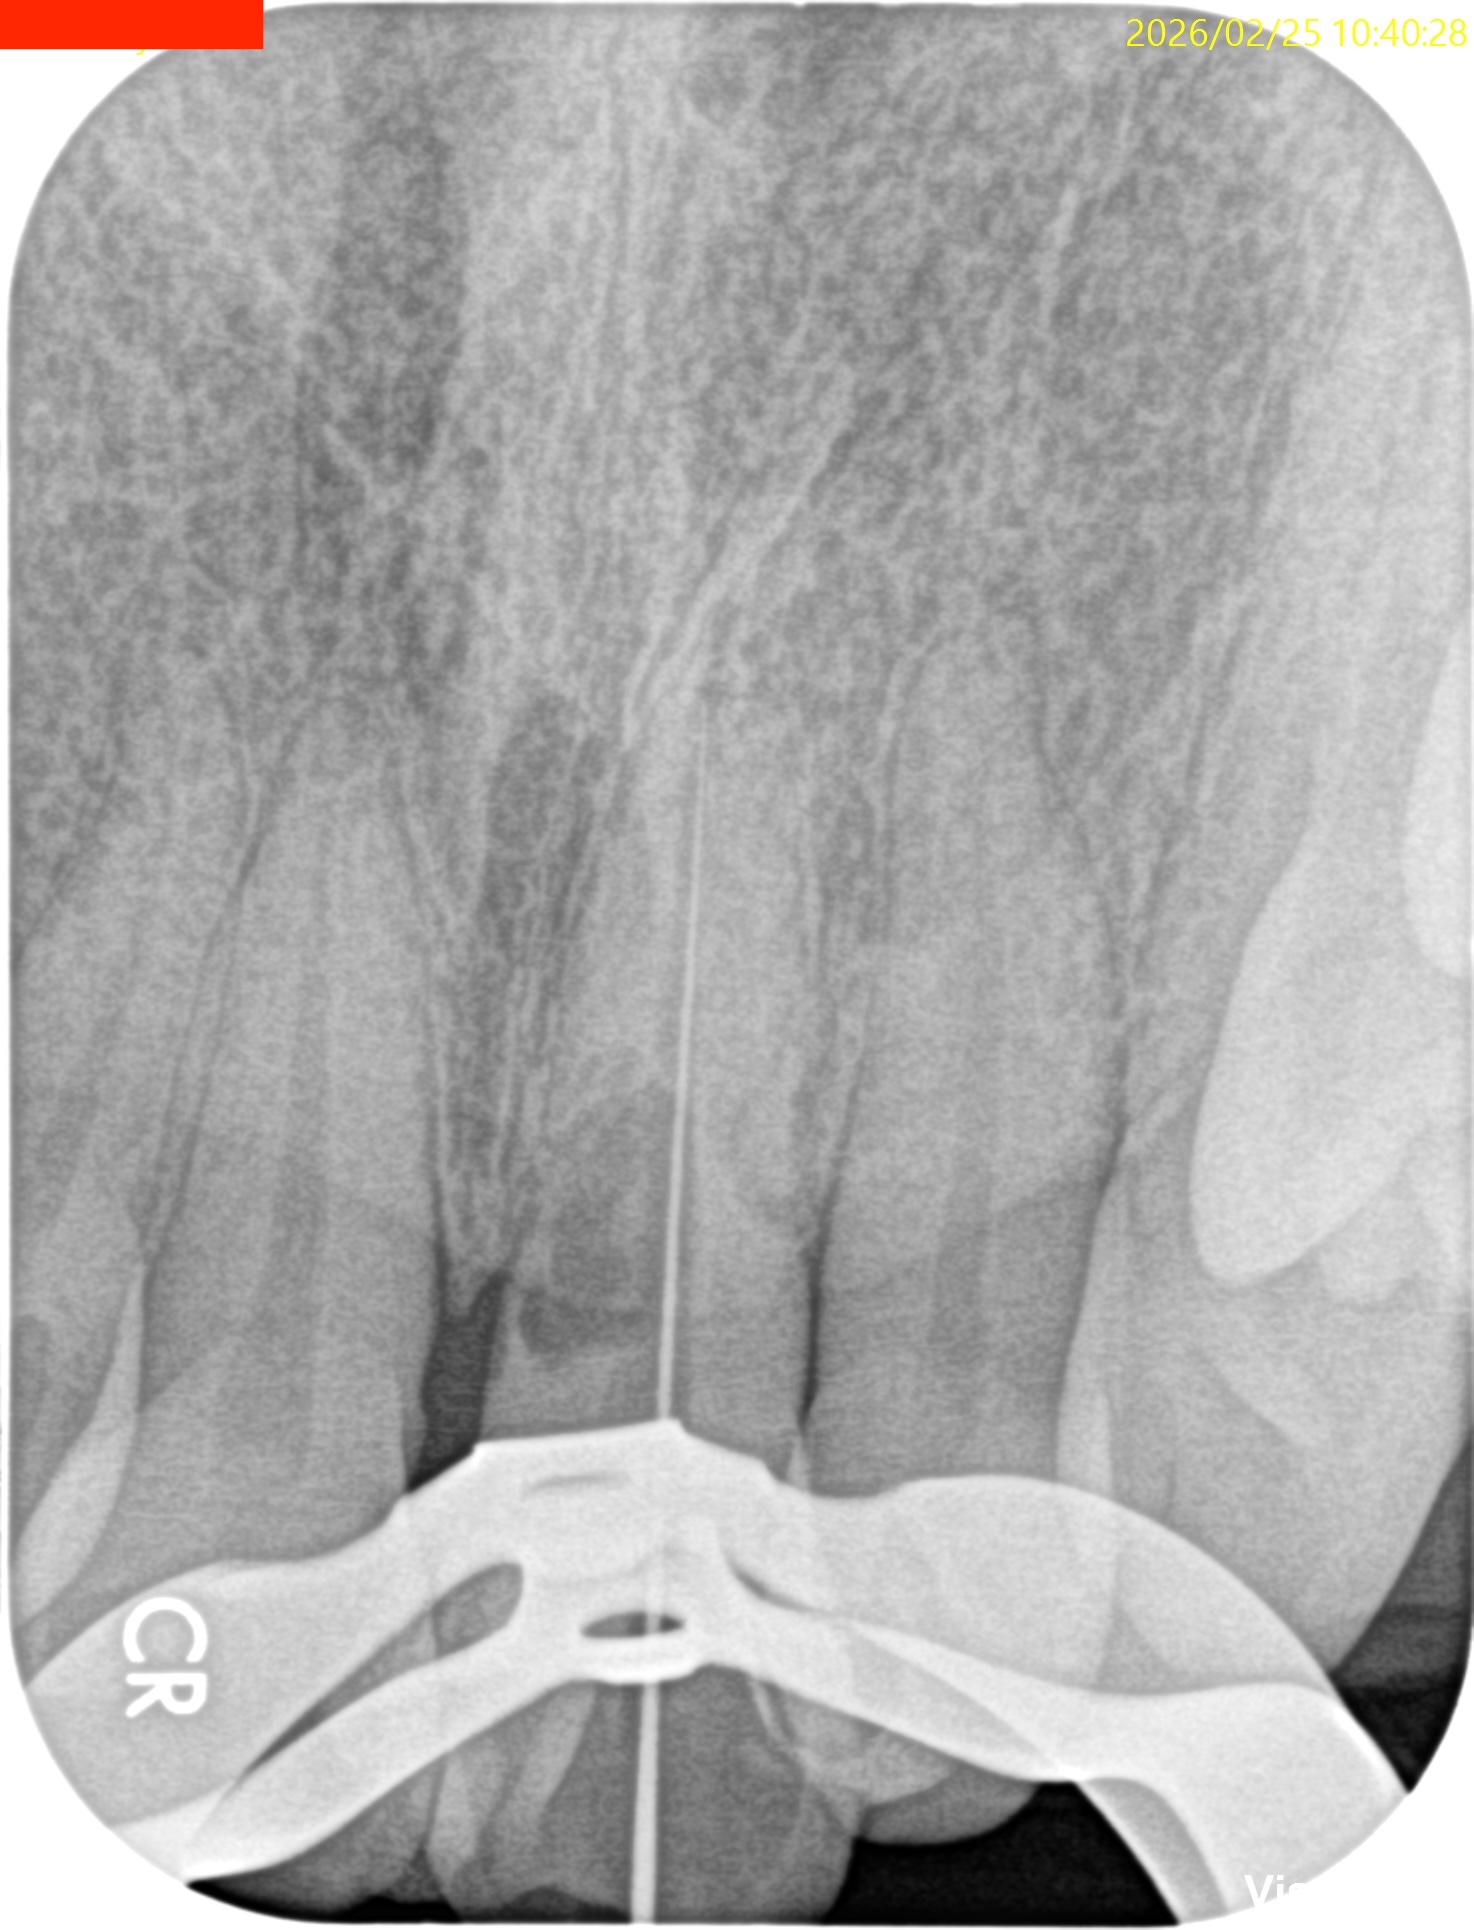

チャンバーオープンし、CBCTから測定した作業長までK Fileを入れてPAを撮影した。

すると…

問題はない位置でFileがストップしている。

CBCTは作業長を求める医療行為にも問題なく使用できるようだ。